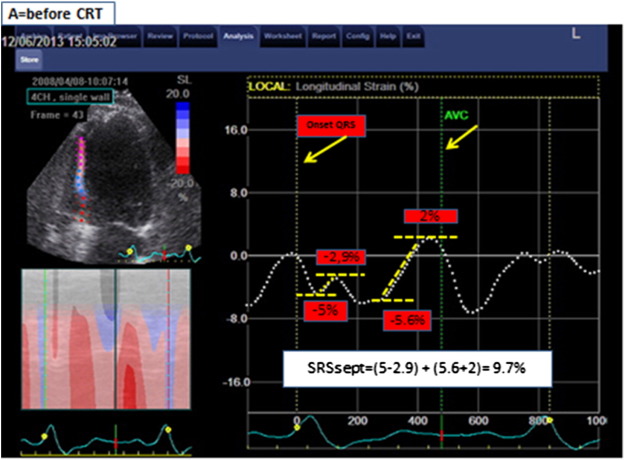

The analysis was performed using EchoPac version 7.0.1, General Electric. The acquisition of the 2D images was performed with at least 40 fps to allow for proper speckle tracking analysis off line. The analysis was performed by a blinded cardiologist to whom only gray-scale imaging of the septal wall and aortic flow recordings was available. Longitudinal speckle tracking technique was used to assess the deformation in the septal wall. The region of interest was set along the endocardial border from the base to the apex, excluding the apical cap, and adapted to match the wall thickness and checked visually and adjusted if necessary. Global wall deformation (i.e., calculated over the entire length of the wall) was used for analysis. SRSsept was defined as the cumulative amount of systolic stretch after prematurely terminated shortening in septum (Fig. 2). The effective septal shortening was defined as the end-systolic (i.e., at aortic valve closure) value of deformation.

Title: Measurement of SRSsept.Legend: Example of septal rebound stretch ...

Fig. 2.

Title: Measurement of SRSsept.

Legend: Example of septal rebound stretch (SRSsept) measurement. Global longitudinal deformation measured over the entire length of the septum is represented by the dash white lines. Negative slope of the deformation curve indicates shortening; positive slope indicates stretching. Systolic stretch that occurs after initial shortening defines systolic rebound stretch. If more than 1 episode of stretch occurs, the absolute amount of stretch is summed to calculate systolic rebound stretch. In this patient with high amount of SRSsept, systolic shortening is interrupted early during systole, resulting in prominent systolic stretching. Note that stretching and shortening occurring after AVC (aortic valve closure) are ignored for rebound stretch measurement.